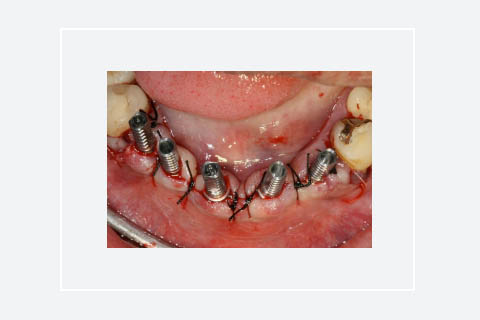

Implants Nobel Active de Ø 3,5 mm posés dans une crête alvéolaire mince. Noter l’expansion de la crête, elle est reconnaissable de par l’épaisseur des lamelles osseuses vestibulaires juxta-implantaires. La table vestibulaire montre des traits de fissure générés par les contraintes exercées lors de la pose des implants. Ils ne constituent pas de menace de perte d'intégrité de la table osseuse.

Mise en place des piliers provisoires pour réaliser une mise en temporisation immédiate au fauteuil. Les sutures sont à distances des piliers, une cicatrisation de seconde intention est visée.